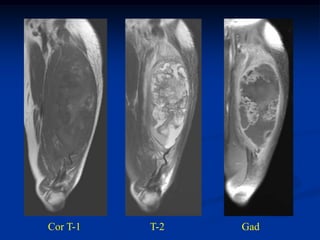

Cor T-2        Two Cor gad              Sag gad

2 yrs later with recurrence above and below the RT ports

Prox thigh axial T-2   Gad

Distal thigh in area

of previous surgery

and 5000 rads RT